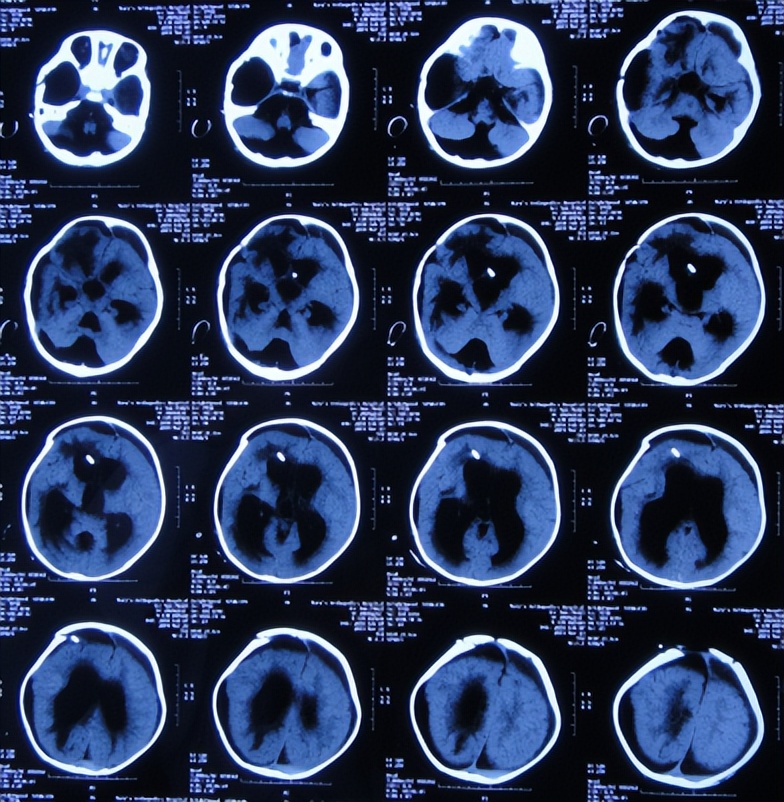

为治疗蛛网膜囊肿、脑积水,于2018年9月13日(发现蛛网膜囊肿后2天),家属带患儿住入第2家医院,湖北省十堰市某三甲医院,查头颅核磁示双颞叶蛛网膜囊肿、脑积水( 图-2 )。

图-2: 2018年9月13日头颅核磁